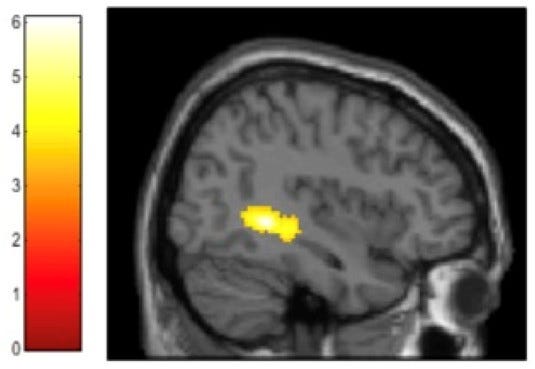

I said they mapped the brain as participants did this reasoning and it is telling.

Above is the right posterior parahippocampus, a part of the brain responsible for contextual associations in episodic memory. Vartanian et al:

Regarding the parahippocampal cortex (PHC) specifically, there is converging evidence to suggest that it plays a critical role in contextual associations—defined as the “link between objects strongly associated with the same context, or the spatial relation between items, or the configuration associated with a context” (Aminoff et al., 2013).

Gemini:

System Disruption: While neutral reasoning typically engages executive control [brain] regions ... the emotional/memory weight of moral injury shifts brain activity toward regions associated with internal distress and memory, leading to logical errors.